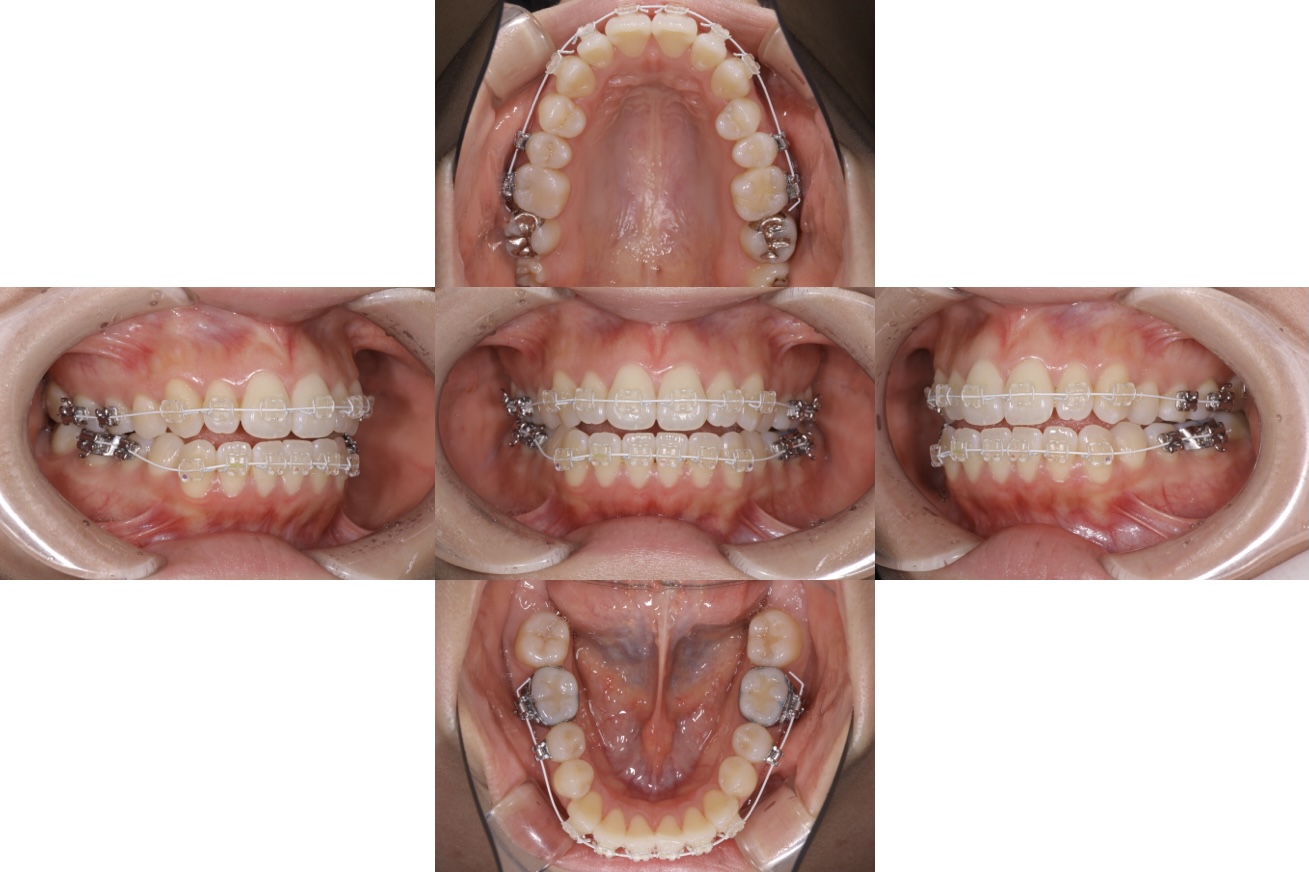

本日は、そんなほのちゃんの[歯並び矯正 途中経過]をお伝えします。

もともと開咬(前歯で噛んでいない状態)だった彼女。矯正を初めて一年弱の現在は…

after

現在は上顎4番を左右とも抜歯をし、前歯の6本を後ろへ動かしている状態です。

変化をあまり感じられないかもしれませんが、犬歯が後ろの方に少し動いています。

急激に歯を動かすと、歯の根っこが短くなったり(根吸収)、歯茎が下がる(リセッション)こともあるので、全ての患者様の負担を出来るだけ減らす形で治療をすすめております。

ゴールにはまだ時間がかかりますが、(機能的にも審美的にも)キレイな歯並びを目指して治療を続けていきます☺️